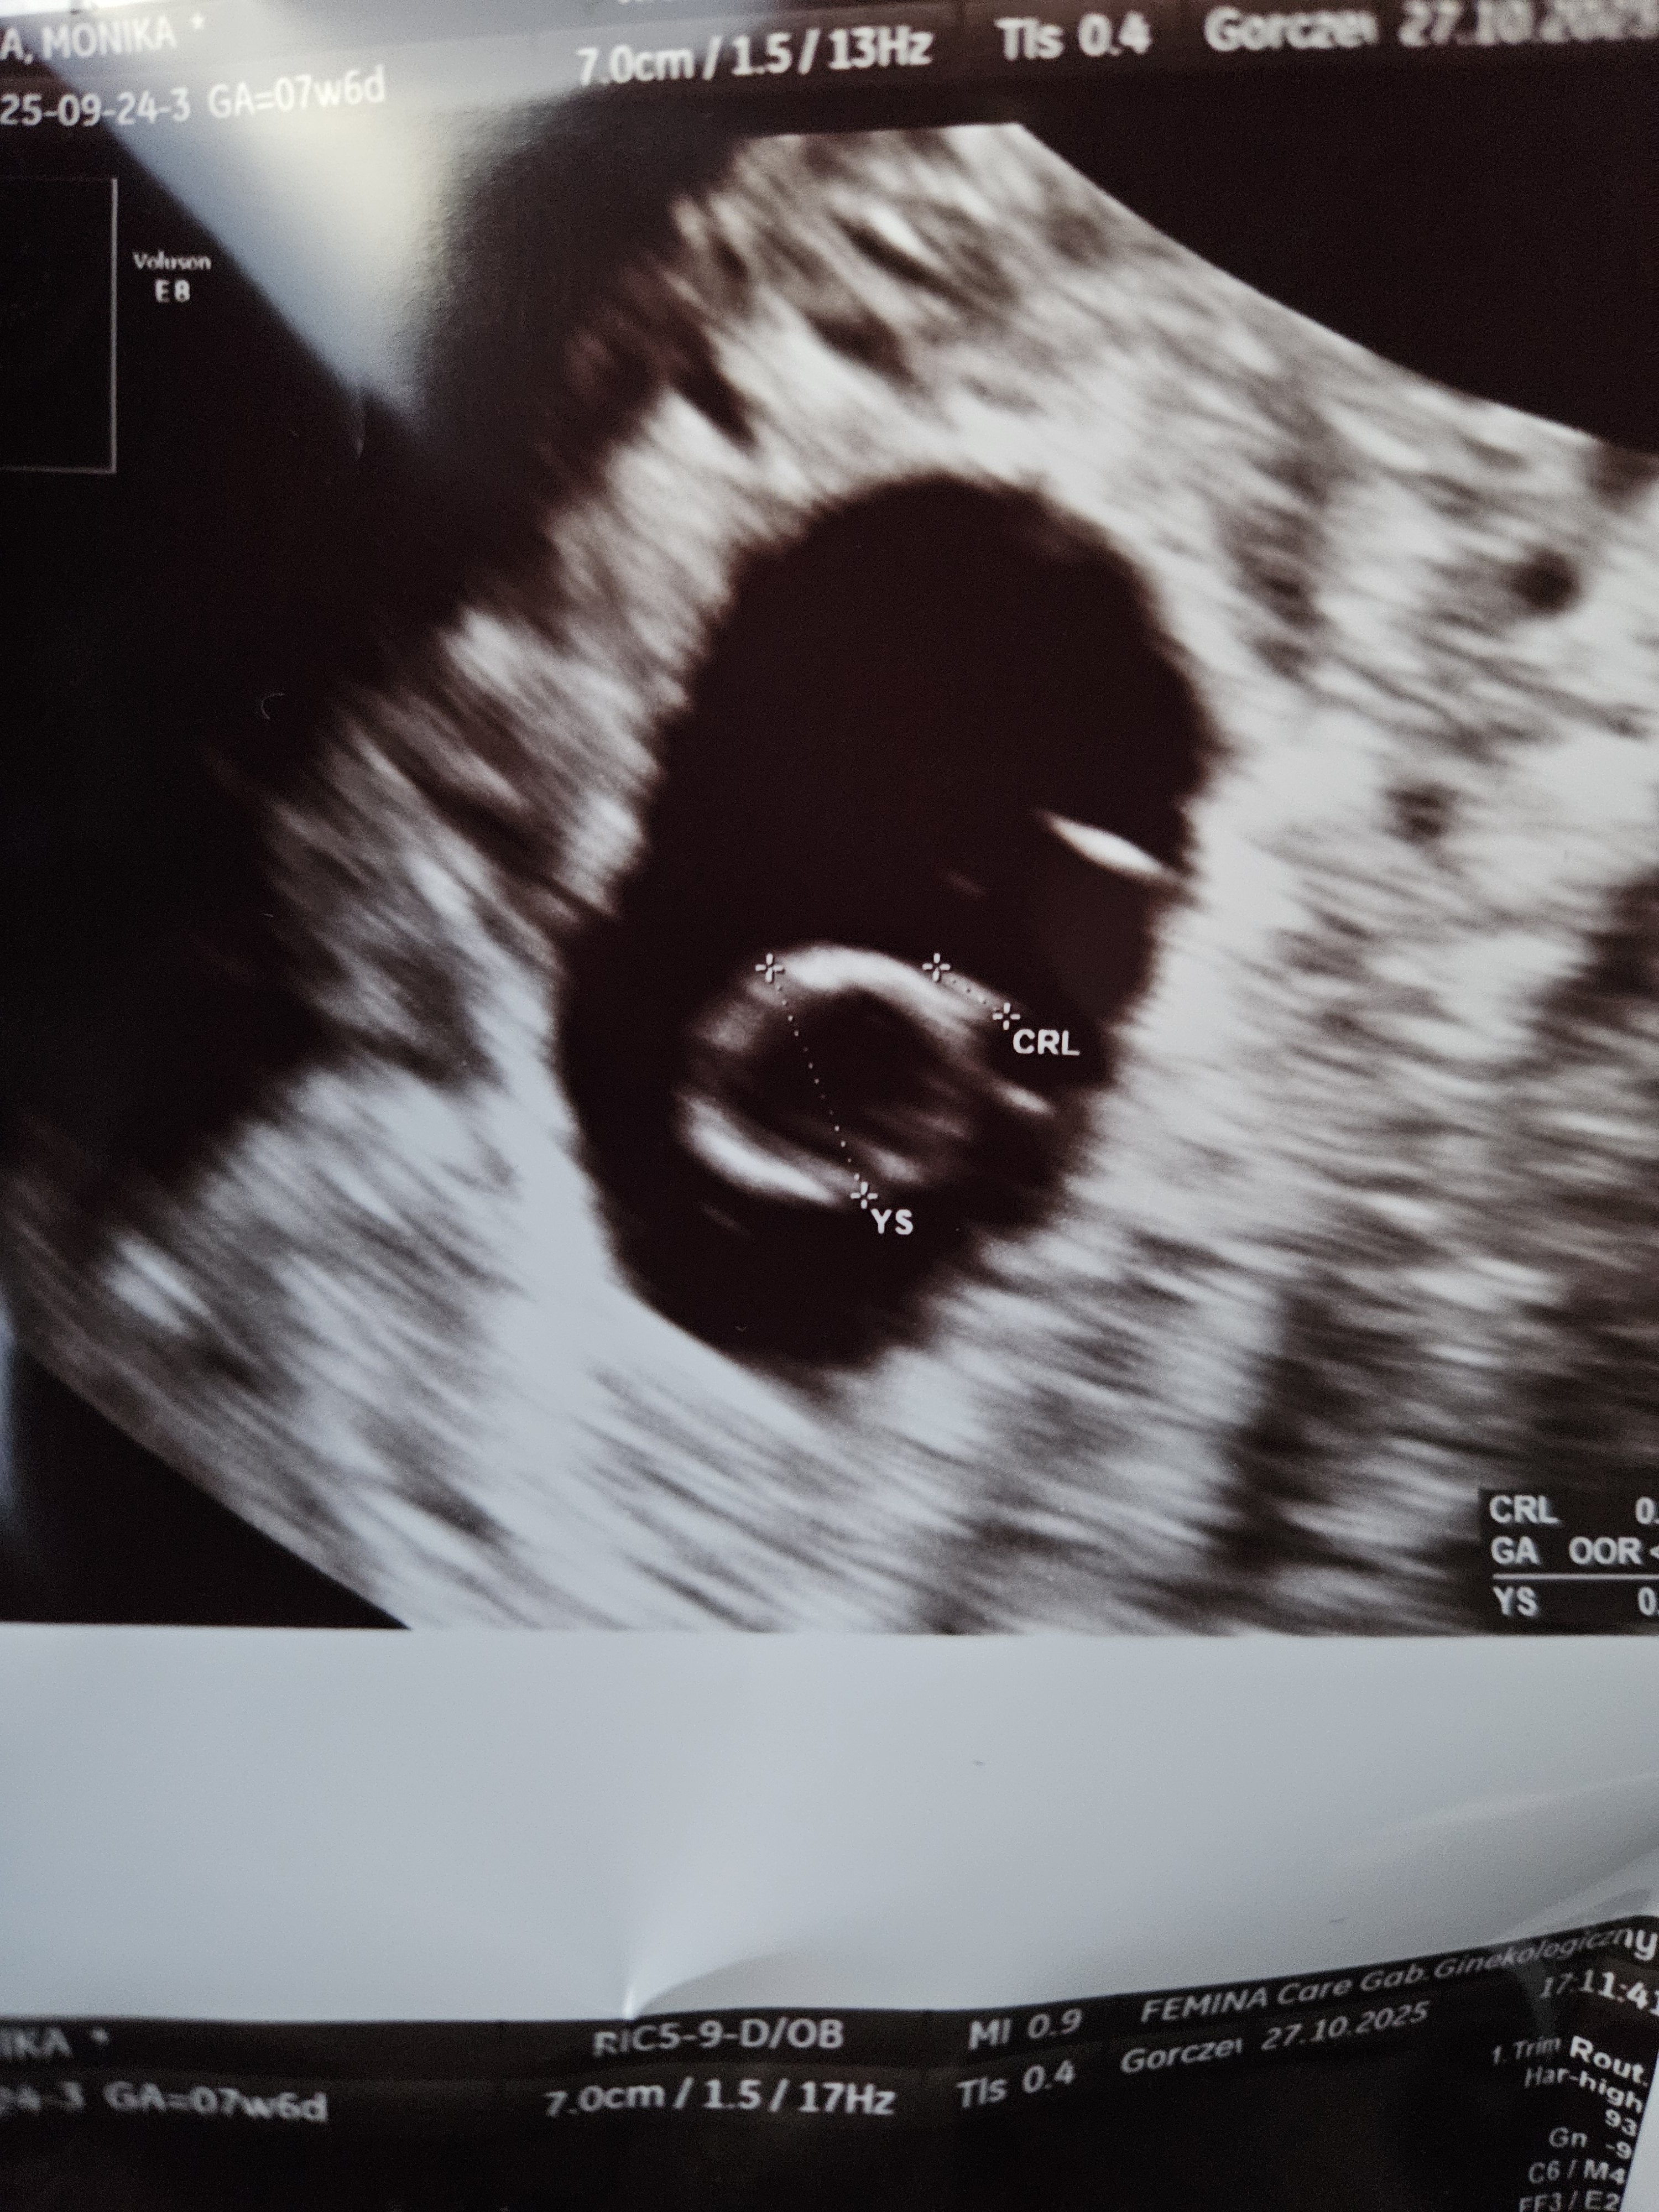

Pokażesz mi jak wygalda obrzęk w 8 tyg ? Tak bo jesteś w 8 ? Bo ja miałam trochę później i jestem ciekawa jak to wygląda wcznsiej wlansieNie wyobrażam sobie co musiałaś przeżyćstaram się nie myśleć i nie nakręcać... ale samo przychodzi. Nie dość że nieplanowana ciąża, to od samego początku coś nie w porządku. Biby beta duża ale przyrost po 48h nie miał nawet 40% . Jajeczko jest, ciałko jest ale ani roz nie odpowiedni ani serduszko i jeszcze ten obrzęk. Mamy konflikt serologiczny, mam niedoczynności i hasi. Nastawiam się negatywnie dla własnego zdrowia psychicznego .

Jutro rano Ci wyślę, nie mam kart ciąży założonej. Tylko zdj i opis. Masz jakieś choroby autoimmunologiczne?Ja nauczona doświadczeniem że jak tak wygalda sytuacja od początku to zazwyczaj nie kończy się dobrze no ale wiadomo ciąża ti nie matematyka może być różnie . U mnie teraz też jest coś chyba nie tak bo crl również się nie pokrywa z wiekiem ciąży